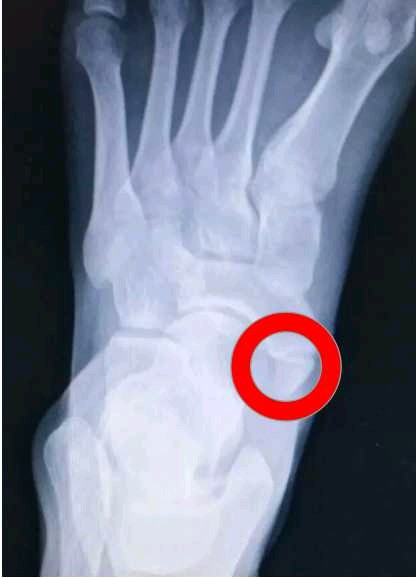

足正侧位X线片及足外侧45°斜位片为首选影像学检查方法,MRI除可发现局部炎症外,还可发现胫后肌腱病变。

一般人一只脚有26块骨头,但是10%~14%的人在足舟骨旁边多出一块骨头--足副舟骨。足副舟骨是一种先天性畸形,由幼年时未能与足舟骨结节相结合的副骨化中心发展而来。位于足内侧、足弓上方。一端通过纤维组织与足舟骨相连接,另一端与其相连的结构可以包括:拇展肌腱、弹簧韧带、部分三角韧带以及胫后肌腱。